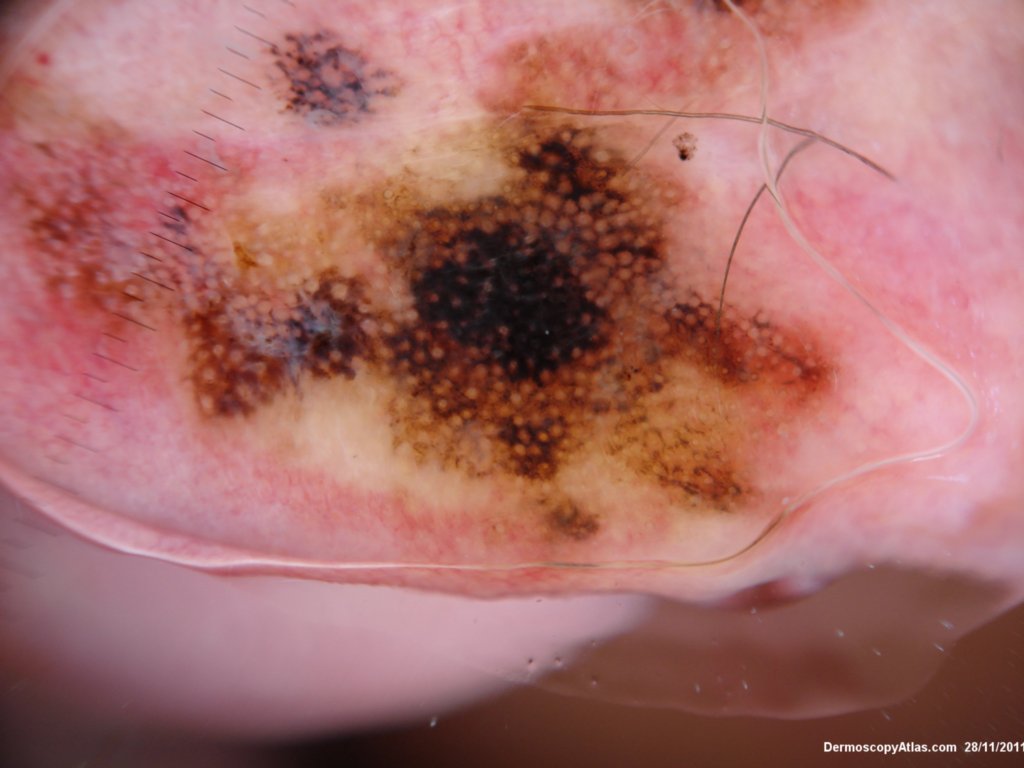

Site: Ear lobe

Diagnosis: Lentigo Maligna

Sex: M

Age: 86

Description: Pigmented lesion on the ear

This elderly male had a pigmented lesion on his ear which was shown to be a lentigo maligna but surgery was refused. It progressed over 5 years as shown but remained a lentigo maligna or melanoma in situ. There is marked perifollicular pigmentation with black structureless areas where the melanoma has obliterated the follicles. Sometimes the terms annular granular structures and rhomboid figures are used along with asymmetrical perifollicular pigmentation to describe these earlier changes. In truth grey circles are often the earliest features of lentigo maligna particuarly on the face.